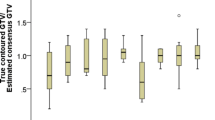

The median absolute percentage differences between observers (interobserver variabilities) were 7.7% (IQR 3.7–15.3%) for manual longest diameter, 3.6% (IQR 0.7–9.3%) for semi-automated longest diameter, and 12.5% (IQR 1.8–30.4%) for volumetric measurements. The median absolute percent differences between reads (intraobserver variabilities) were 5.0% (IQR 2.3–9.7%) for manual longest diameter, 3.9% (IQR 1.5–8.6%) for semi-automated longest diameter, and 10.7% (IQR 4.2–24.3%) for volumetric measurements. The inter- and intraobserver variability of the manual measurements of the longest diameter were higher (though not all statistically significant at all dose levels) than that of the semi-automated measurements (p < 0.001 for overall). The inter- and intraobserver variability were higher for the volumetric measurement, compared to both manual and semi-automated measurements of the longest diameter (p < 0.001 for overall; Fig. 2a, b).

Box plots show interobserver variability (a), intraobserver variability (b), and dose variability (c). The variability related to radiation dose was not significantly different from inter- and intraobserver variability for both manual and semi-automated measurements of the longest diameter. The variability related to radiation dose for volume measurements was statistically higher than that of inter- and intraobserver variability at 50% and 100% dose levels. *p value < 0.05, **p value < 0.001. p values are from Wilcoxon rank-sum tests

The median absolute percentage differences between dose levels (dose variabilities) were 4.5% (IQR 1.9–8.6%) for manual longest diameter, 5.6% (IQR 2.3–11.4%) for semi-automated longest diameter and 13.6% (IQR 5.7–28.4%) for volumetric measurements. There was a trend toward higher variability with decreasing radiation dose for both manual and semi-automated measurements of the longest diameter and volume (Table 1).

In regression models, quantitative measurements were only statistically different at 25% and 37.5% radiation dose levels for the semi-automated measurements of the longest diameter, as well as at 25% radiation dose level for semi-automated measurement of the volume (Fig. 2c). There was no significant difference in the variability of measurements of the longest diameter and volume between the two commercially available semi-automated segmentation software (Table 2).

The variability related to changes in radiation dose was comparable to the inter- and intraobserver variability for both the manual and semi-automated measurements of the longest diameter (p > 0.0008 with Bonferroni correction). However, the variability related to changes in radiation dose for volume was significantly higher than that of inter- and intraobserver variability at 50% and 100% dose levels (p < 0.0008 with Bonferroni correction) (Table 3).